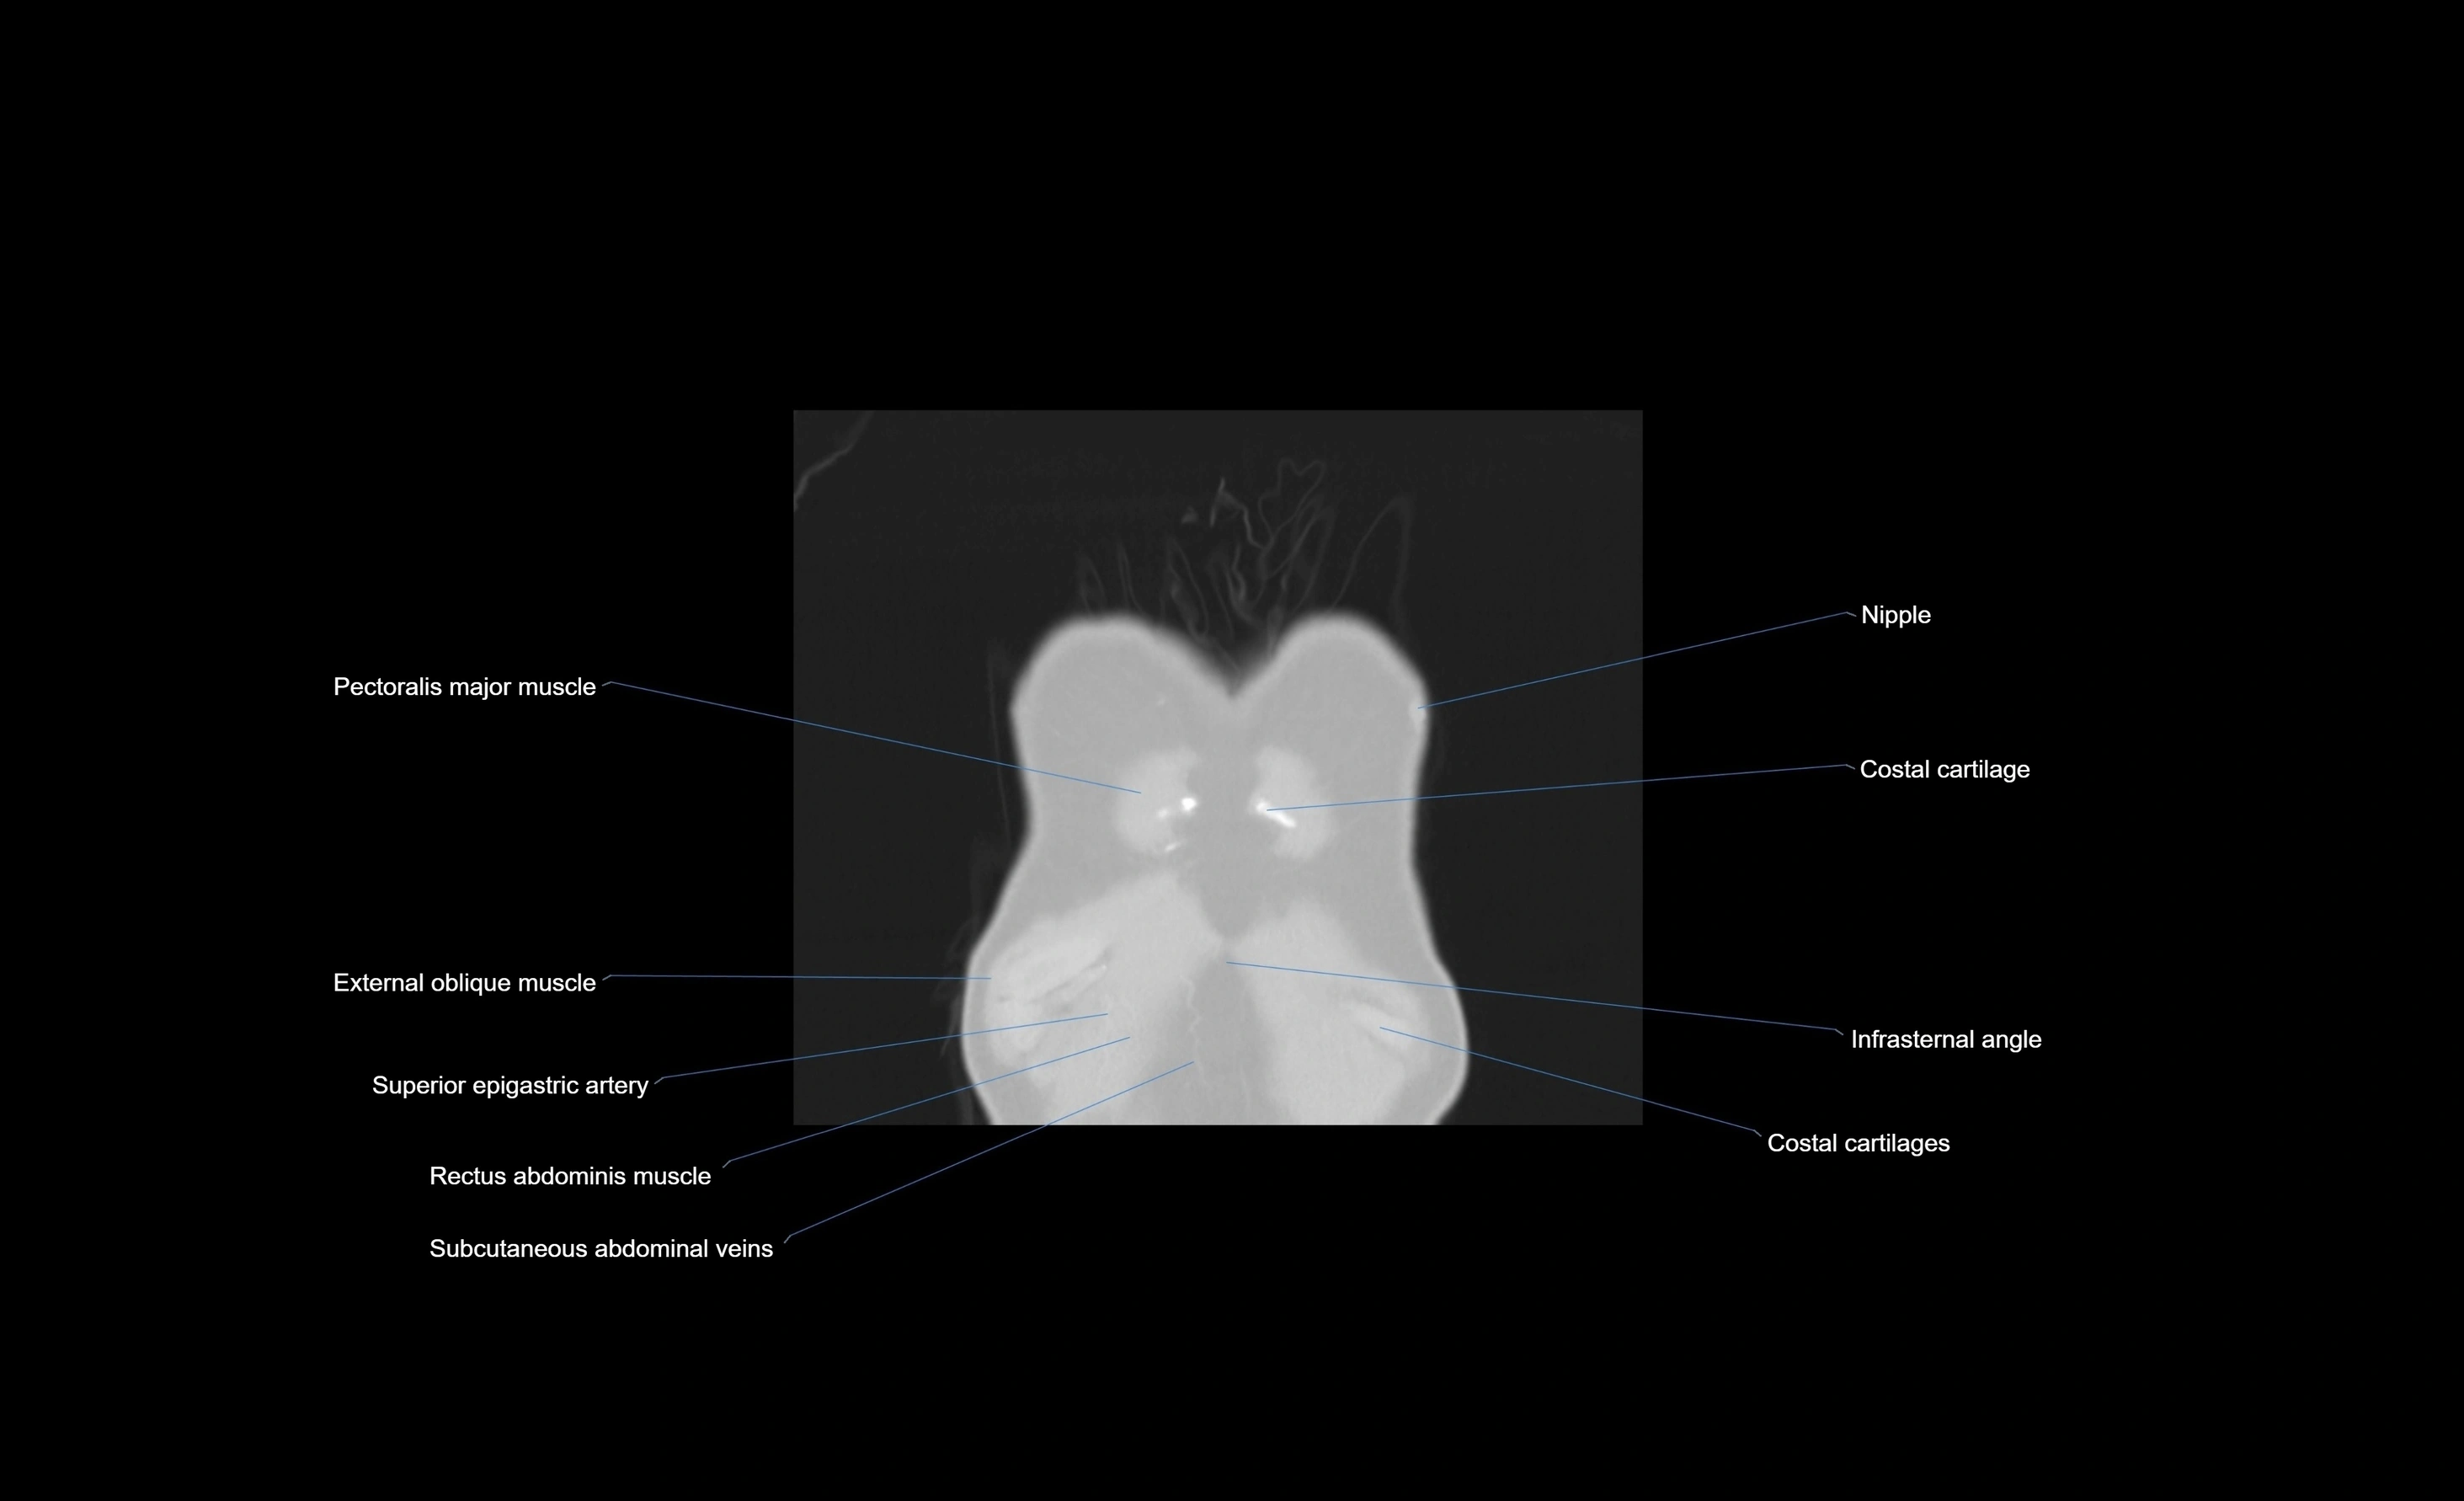

- Superior epigastric artery

- Superior epigastric veins

- Rectus abdominis muscle

- External oblique muscle